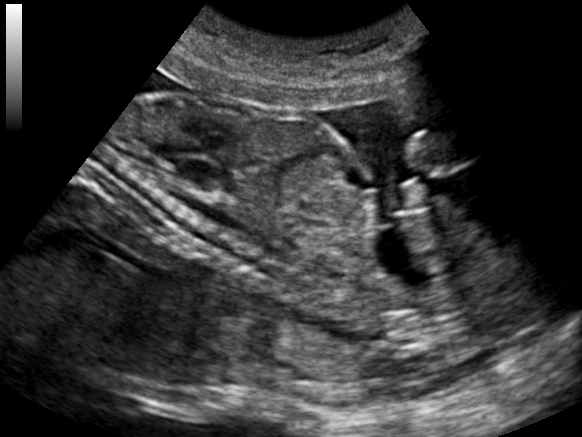

4. 추가 이미지